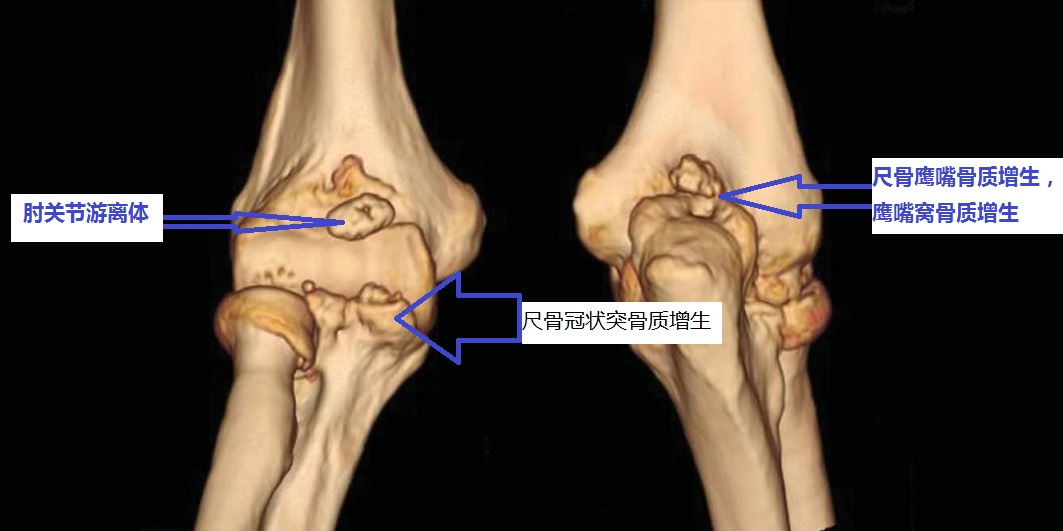

为什么您的肘关节伸不直呢?

伸不直往往是因为:1、尺骨鹰嘴骨质增生;2、肱骨远端后侧的尺骨鹰嘴窝骨质增生填塞;3、肘关节前侧的关节囊挛缩;4、肘关节内的游离体卡住了;等等。

为什么您的肘关节屈不下来呢?

屈不下来往往是因为:1、尺骨冠状突骨质增生;3、肱骨远端前面的尺骨冠状突窝骨质增生;4、肘关节后侧的关节囊挛缩;等等。